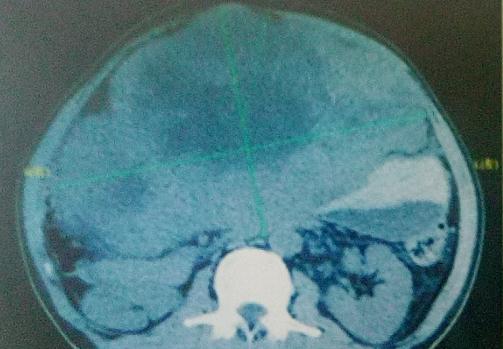

患者于2015年1月2首次入我院。入院时进食稍差,有呕吐,乏力症状,大小便未见异常,体重较前下降约15kg。腹部超声提示:肝左叶体积明显增大,形态失常,可探及多发稍高回声团块,较大者呈“巨块型”,长径30cm,明显外凸,占据整个中部腹腔,边界不清,形态不规则。

完善各项入院检查后,行缓释库治疗多次,于2015年10月1日复查腹部CT:肝左叶巨大肿块,肝肿瘤明显缩小,最大截面约13.5cmx 11.1cm。AFP下降至400.01ng/ml.治疗后体重增加10kg。